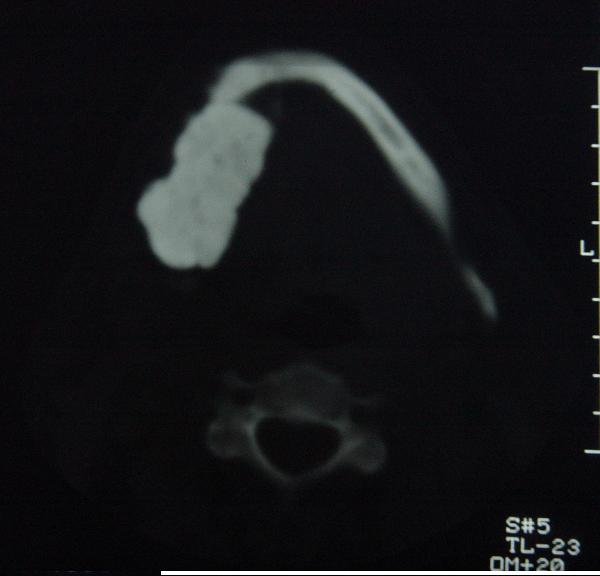

标题: CT12465:下颌骨肿瘤,请会诊 [打印本页]

标题: CT12465:下颌骨肿瘤,请会诊

发现下颌骨肿瘤近30年.逐渐增大.

考虑右侧下颌骨水平部及升部骨纤维异常增殖症可能性大。

考虑右侧下颌骨骨化性纤维瘤。